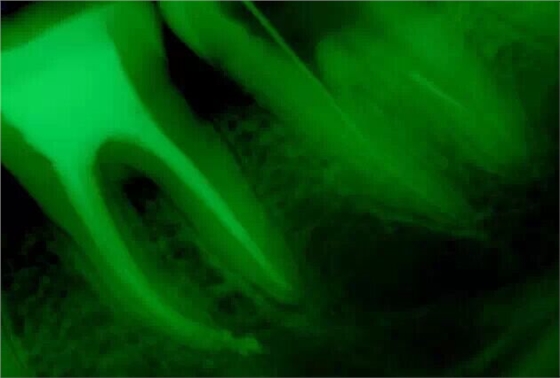

取出斷針時的X片